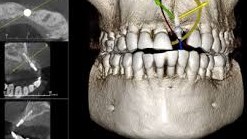

Unlike traditional X-rays that capture flat, two-dimensional images, a dental CT scanner takes things to a whole new level. Imagine a machine that can capture hundreds of images from different angles, all in a single scan. This data is then used to create a 3D digital model of your jaw, teeth, nerves, and surrounding tissues. It's like having a virtual map of your mouth, allowing dentists to see intricate details that would be invisible with a regular X-ray.

Implant Planning: Dental implants are a popular solution for missing teeth, but precise placement is crucial for success. A CT scan provides a clear view of the jawbone, allowing dentists to plan implant surgery with unmatched accuracy, minimizing risks and ensuring optimal outcomes.

Wisdom Teeth Wisdom: Wisdom teeth removal can be tricky due to their location and potential proximity to nerves. A CT scan helps dentists assess the position of wisdom teeth and plan the safest extraction route.

TMJ Diagnosis: Temporomandibular joint (TMJ) disorders can cause pain and headaches. A CT scan can provide detailed images of the jaw joint, aiding in diagnosing TMJ issues and developing effective treatment plans.